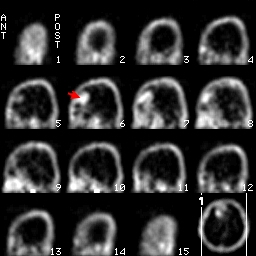

這是一個right frontal Lobe發現腫瘤的圖片,在這3個方向的切面中都能夠見到在大腦右前葉處出現了Tc-99m-DTPA的堆積影像,另外一張圖則是利用透視法所處理出來的3D影像,清楚的顯現出腫瘤的位置。

矢狀切面sagittal